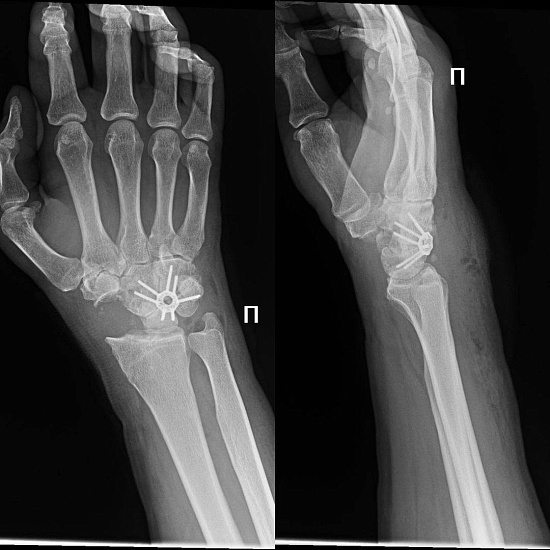

Пациент обратился к Гайку Кареновичу с жалобой на боль и ограничение подвижности в лучезапястном суставе.

Анамнез: около 15 лет назад получена травма – перелом, про который пациент знал, но не лечил руку.

• Из-за нарушения положения костей, в запястье развился артроз, который еще больше нарушил положение костей. Цикл неоднократно повторялся, и с каждым новым витком проблема усугублялась.

• Функция кисти пострадала, что привело к болезненности и ограниченности движений.

Для решения проблемы Гайк Каренович выполнил операцию – парциальный артродез.